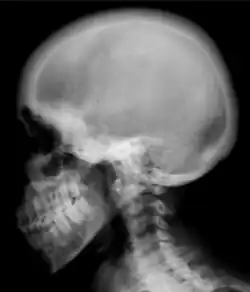

![Ground glass density of the skull.[18]](./_assets_/X-ray_of_ground_glass_density_of_the_skull_by_renal_osteodystrophy.jpg) Ground glass density of the skull.[18] Ground glass density of the skull.[18]